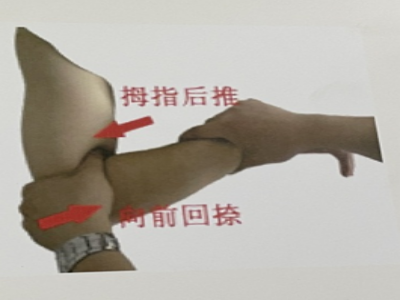

1.旋前屈肘牵引提端挤推极度屈肘

整复过程中的分解动作,在实际操作时,一气呵成。复位后,术者将患肢前臂保持在旋前位、屈肘120°整复成功后,术者将患肢保持在前臂旋前位屈肘120°,助手站干患肢外侧,伤处敷贴金黄散软膏,内衬2~3层桃花纸,按内、外、后、前的顺序放夹板。夹板间留1cm的间隙,然后用1cm宽的胶布与6*10棉纱绷带缚扎。杉树皮固定松紧适宜,密切关注末端血运,如有不适及时复诊。